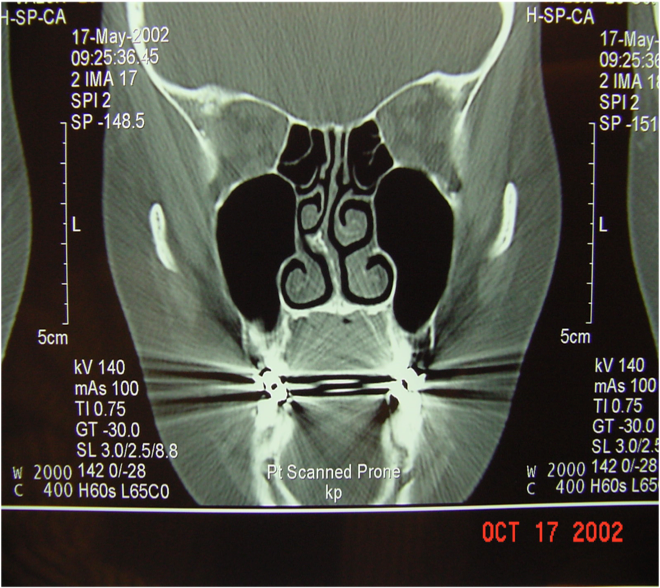

- Anatomic changes (e.g., deviated septum, concha bullosa, polyps).

- Concha bullosa.